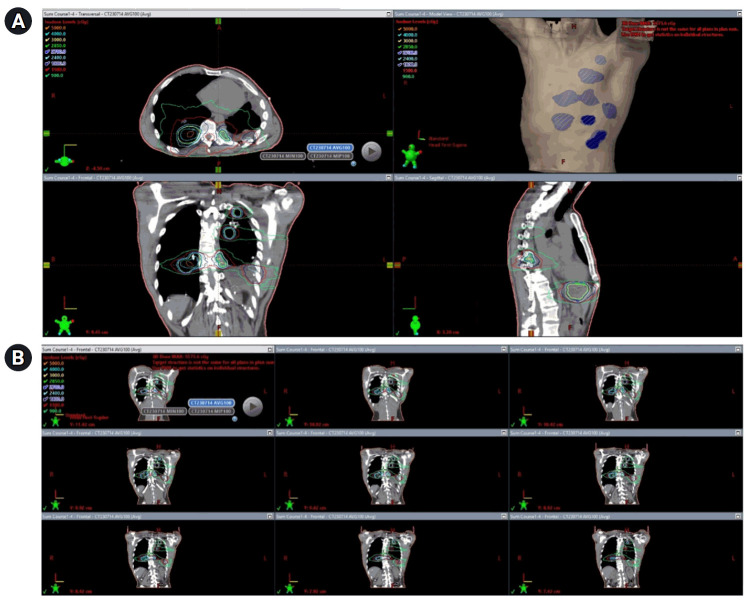

腺样囊性癌是一种难以治疗的恶性肿瘤,通常会转移到肺部。全身化疗对这种肿瘤类型无效,因此经常使用局部疗法。在此,我们报告了一个病例,该病例展示了广泛消融干预在控制转移性腺样囊性癌进展方面的应用。一名腺样囊性癌患者的肺部和肝脏出现了大量转移灶。在长达十年的时间里,他采用了包括间质近距离放射治疗和 SBRT 在内的局部消融疗法,治疗了大约 80 个不同的转移灶。该患者体内植入了 850 多颗近距离放射粒子,肿瘤控制和患者预后良好。截至 2024 年 3 月的最近一次随访,该患者自确诊腺样囊性癌以来已存活了约 12 年。据我们所知,该病例是报告的单个患者接受近距离放射治疗次数最多的病例。它凸显了间质近距离放射治疗和 SBRT 在治疗广泛的肺和肝转移瘤方面的实用性。

Adenoid cystic carcinoma is a malignancy that is difficult to treat and often metastasizes to the lung. Systemic chemotherapies are not effective for this tumor type, thus local therapies are frequently used. Here, we report a case demonstrating the use of extensive ablative interventions in controlling the progression of metastatic adenoid cystic carcinoma. A patient with adenoid cystic carcinoma developed numerous metastases to his lungs and liver. Local ablative therapies including interstitial brachytherapy and SBRT were used to treat approximately 80 different metastases over the course of a decade. Over 850 brachytherapy seeds were implanted in this patient, and the tumor control and patient outcome were good. As of the most recent follow-up in March 2024, the patient has survived for approximately 12 years since his diagnosis of adenoid cystic carcinoma. To our knowledge, this case represents the most brachytherapy treatments reported in a single patient. It highlights the utility of interstitial brachytherapy and SBRT in treating extensive lung and liver metastases.